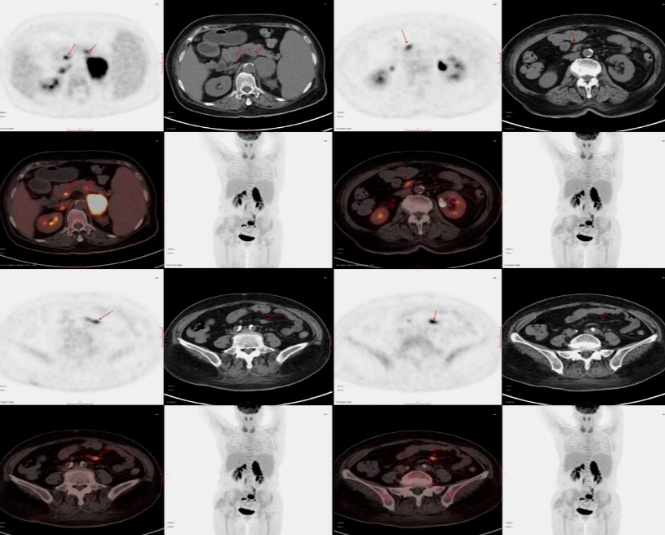

脑、肾上腺、肝……病灶似乎无处不在,却又来源不明。为了揭开这层迷雾,我院迅速组织了多学科会诊,并建议患者进行PET/CT检查,以全面评估全身情况。这一查,果然发现了关键线索:除了已知病灶,PET/CT还清晰地捕捉到腹腔、腹膜后多发淋巴结、腹部静脉乃至骨骼上的多处高代谢灶。

核医学科医师团队综合影像特征,给出了关键判断:这极可能是一种能累及全身的血液系统恶性肿瘤——淋巴瘤。最终,通过肾上腺肿物穿刺活检,病理结果证实了PET/CT的推断:非霍奇金淋巴瘤(弥漫大B细胞淋巴瘤),患者随即转入淋巴瘤血液科接受下一步精准治疗。